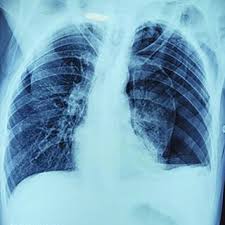

2) X-ray 촬영

가장 흔히 시행되는 진단 방법은 흉부 X-ray입니다. 금이 심하지 않으면 X-ray에서 보이지 않을 수도 있습니다. 단순 촬영의 한계 때문에 증상이 심하면 다른 검사를 병행합니다.

하지만 초기 확인을 위해 꼭 필요한 기본 검사입니다. 대부분 응급실이나 외래에서 바로 진행됩니다.